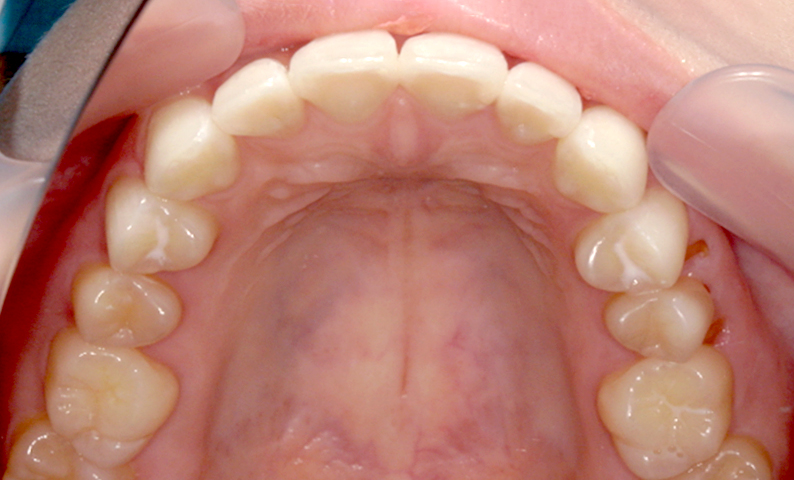

症例_006 前歯「捻転歯」症例

治療期間:7ヶ月金額:30万円+税20代女性少しのねじれ歯の形態修正上の前歯だけ

| Before | After |